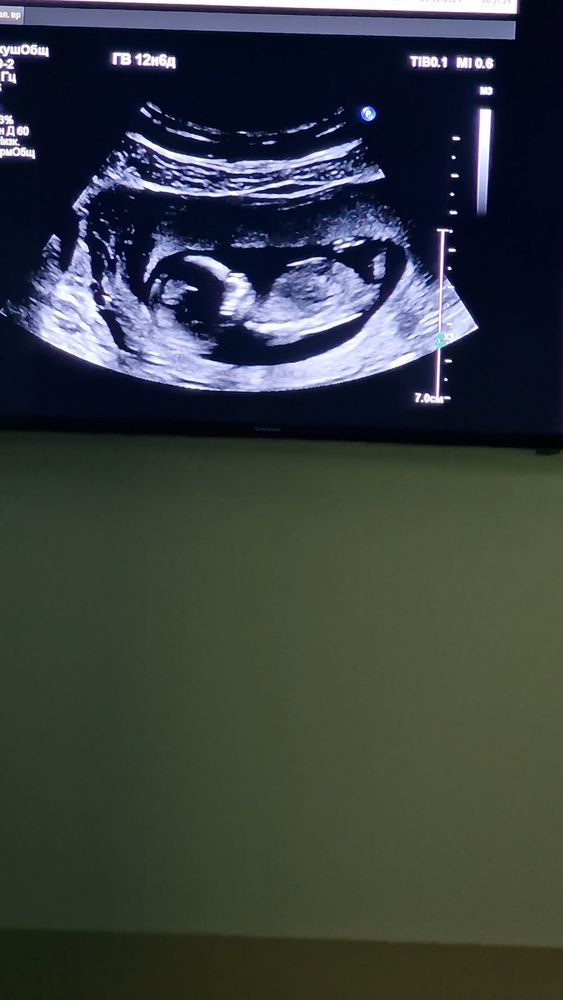

1 скрининг 🥳🥳🥳 нам 13 недель

Копчико- теменной размер 66мм

Чсс 166 ❤️

Воротничковая зона 1.9 мм

Кости носа 2.3мм

Шейка матки 37мм , но тонус повышен по 3/ стенке.